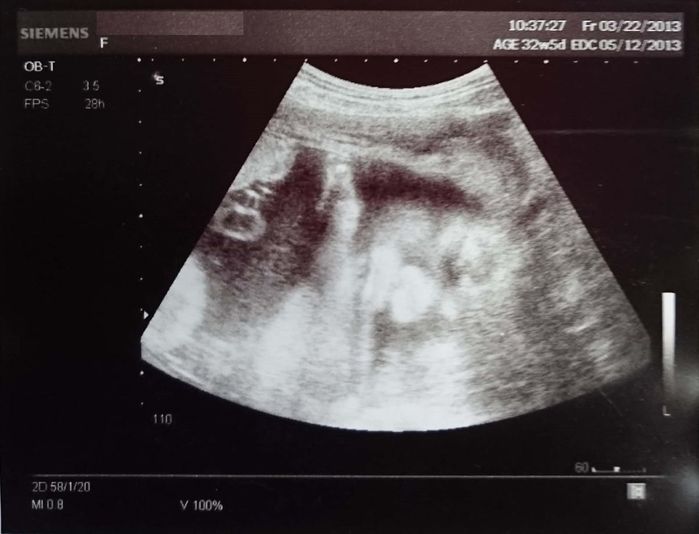

妊娠32週のエコー写真 白黒エコー写真なのにわかる、夫にそっくりな鼻

白黒写真であるにもかかわらず、真正面の顔が撮れたために、鼻の形が夫にそっくりなことが判明。右側に横になって目を閉じ、腕を顎に乗せているようですが、真ん中の白くおにぎりのような三角が鼻です。その左のたらこのようなものが唇。この口の形も夫にそっくり。特に夫の赤ちゃんの頃に似ていました。実際に生まれた時の顔はもっとほっそりしていましたが、鼻はこのままでした。